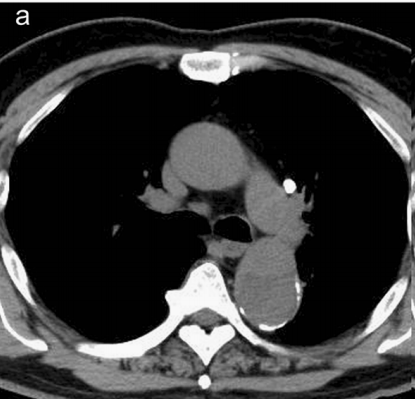

图12

不行,你再看看,越看越像!

图13

增强CT一看,主动脉的确裂开了!

图14